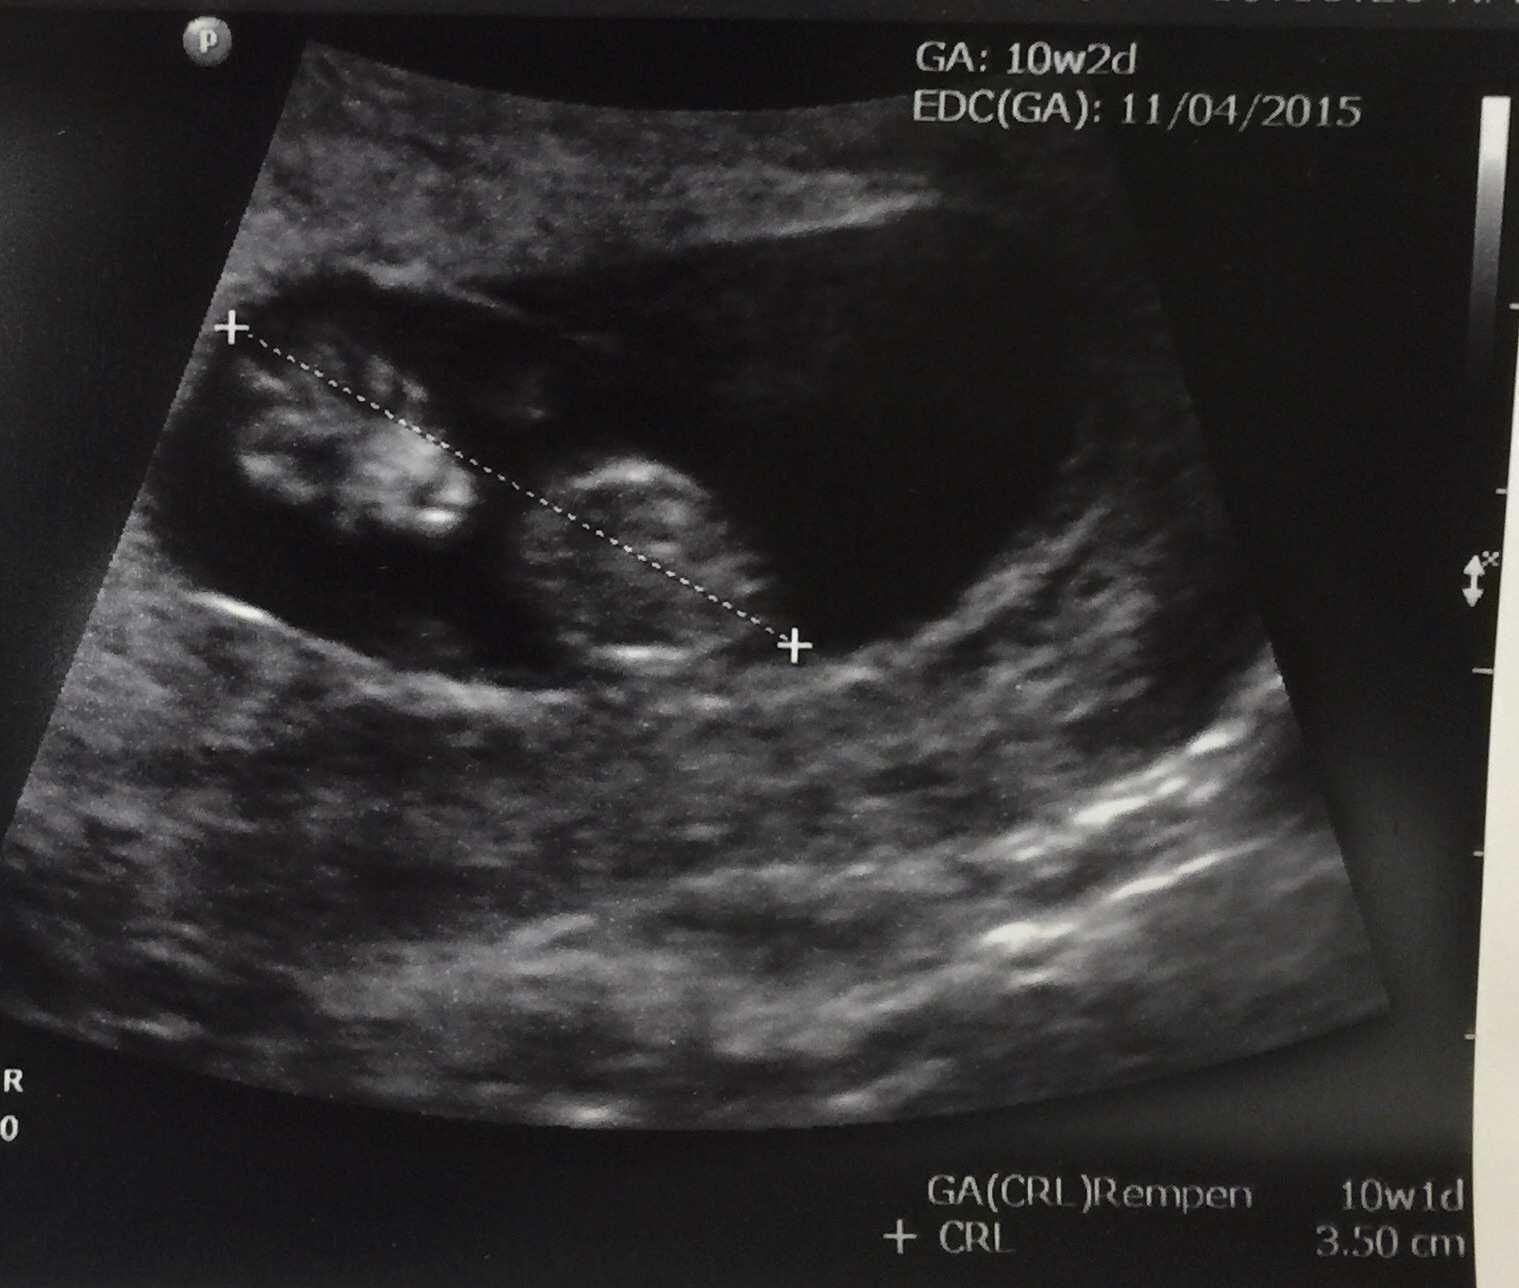

Our 10 week scan that we had this last Tuesday 4/7. Baby measured 10w5d with a heartbeat of 160 bpm. It was a great day for husband and I, not to mention how adorable those little wiggle wiggles were. omgosh, just melted my heart. I am so in love